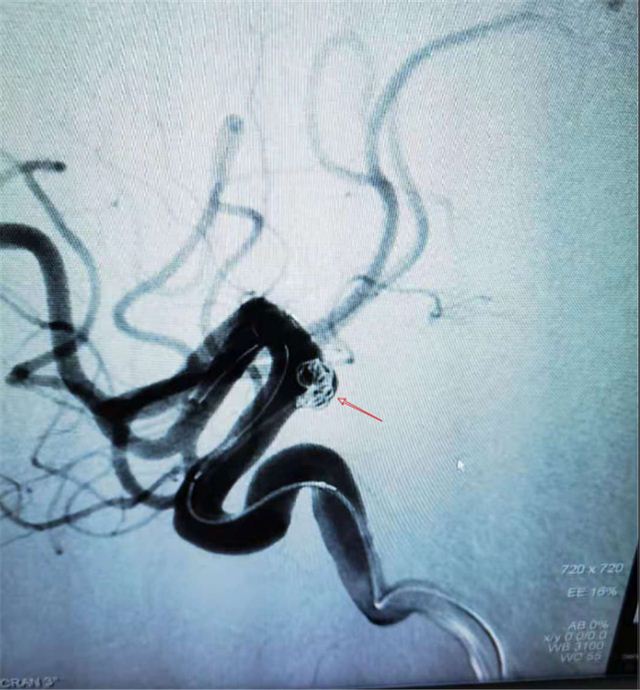

外一科医务团队有条不紊进行术前准备、并做好术后相关并发症的预案处理。经过泉州市第一医院神经外科余惠平主任的指导,外一科医务团队成功完成气静复合麻醉下行经皮股动脉穿刺全脑血管造影术+左侧颈内动脉后交通动脉段动脉瘤支架辅助栓塞下弹簧圈介入栓塞术。

DSA下动脉瘤定位

手术顺利,DSA辅助下精准定位"不定时炸弹",动脉瘤内填塞弹簧圈,阻断冲击动脉瘤的血流。术后患者神志清楚,拔除气管插管后返回病房,术后24h后即可下床活动,术后1周出院。